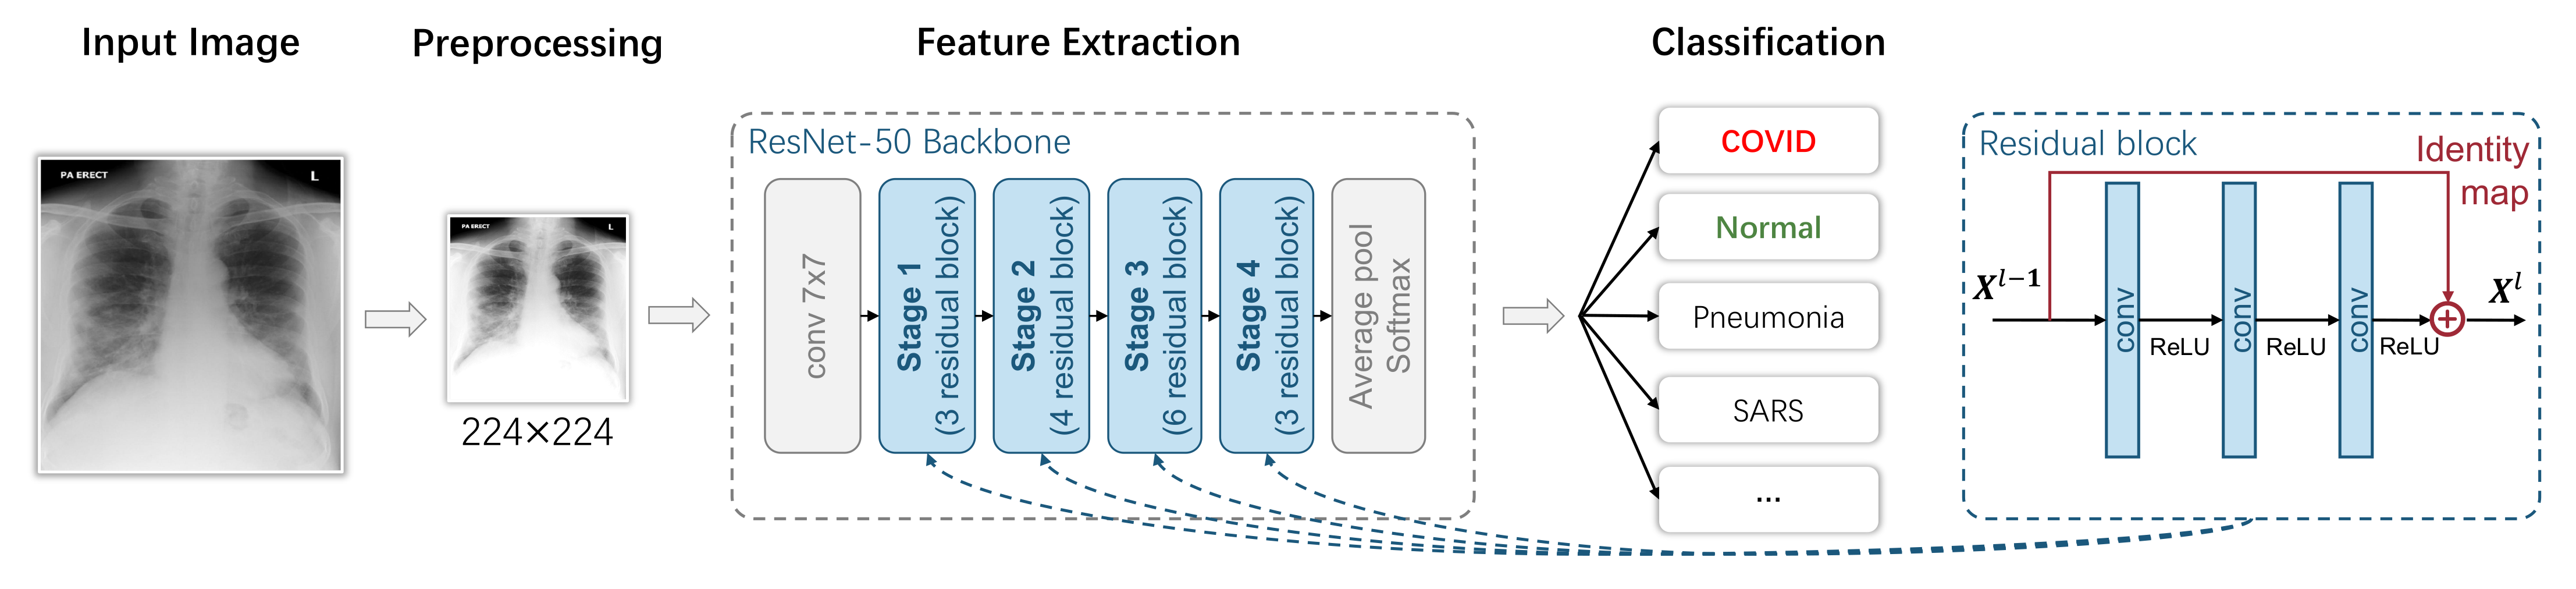

3.1. Image-Level Diagnosis: Classification-Based Models

3.1.1. Overview

3.1.2. Preprocessing

3.1.3. Feature Extraction

3.1.4. Classification